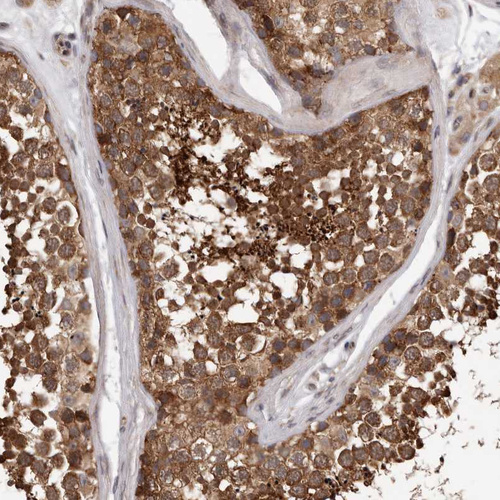

Immunohistochemical staining of human testis shows strong cytoplasmic positivity in cells in seminiferous ducts.